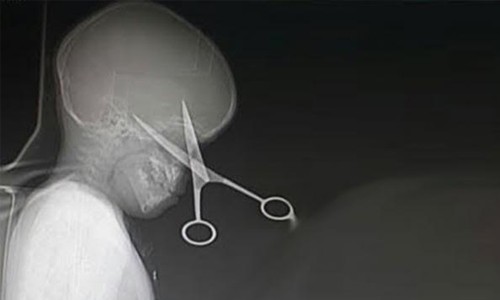

Scissors removed from child's head

Saudi surgeons removed a scissors from a child’s skull after it penetrated his head while he was playing at home in the Gulf Kingdom.

Doctors in the Western Red Sea port of Jeddah said they performed a three-hour operation to remove the scissors which images showed it pierced deep into the skull.

Ajel newspaper quoted anesthesia specialist Dr Ahmed Zaki at King Fahd Hospital as saying the operation was successful and the child was in a stable condition.

The paper said the little boy was playing on the table at his home when he fell down while he was clutching a scissors in his hand.